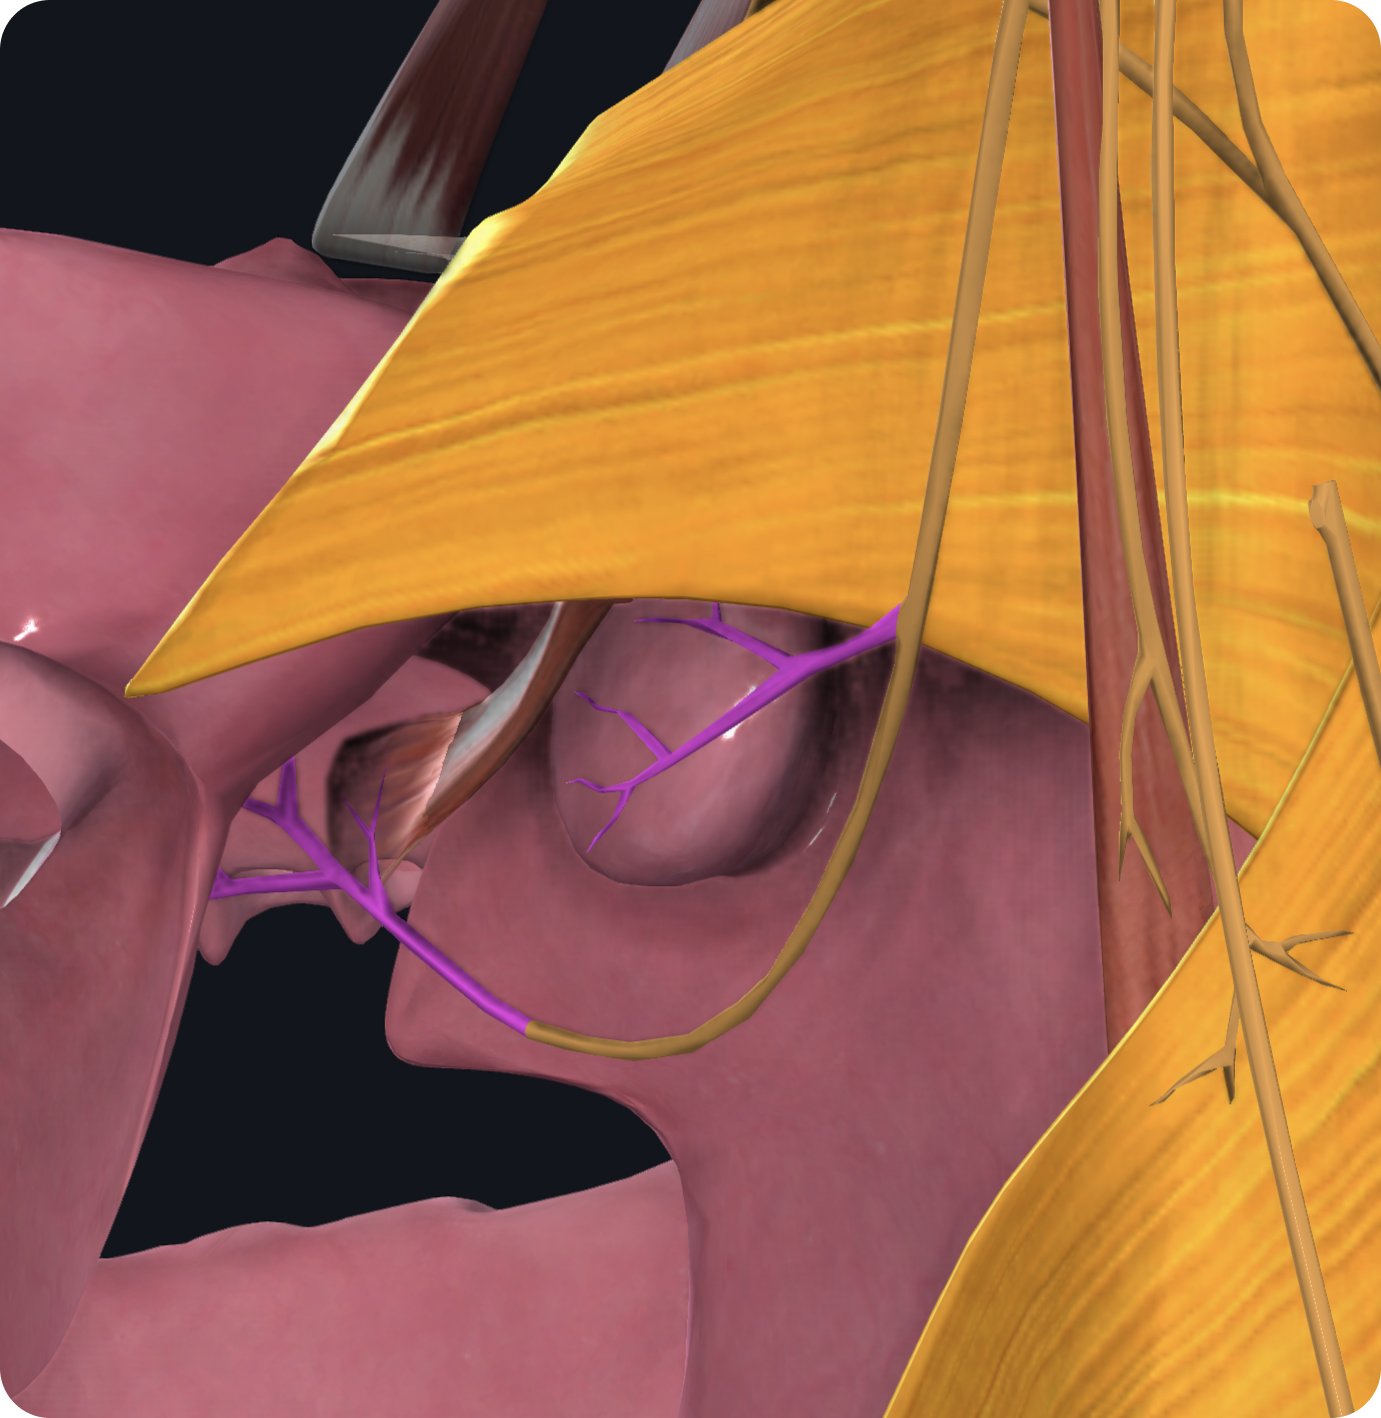

The glossopharyngeal nerve gives off a fourth branch the stylopharyngeal branch which wraps around the stylopharyngeus muscle providing motor innervation to this muscle.

The glossopharyngeal nerve then passes into the space between the superior and middle pharyngeal constrictor muscles where it gives off two more small branches.

The tonsillar branch carries sensory nerve fibers from the palatine tonsils.

The lingual branch carries special sensory taste fibers from the posterior third of the tongue and provides sensation to this area.